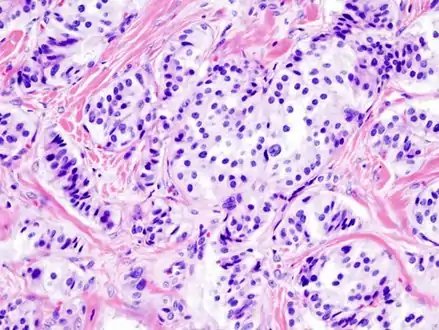

| Pathology of pancreatic endocrine tumour (insulinoma). | |

Pancreatic insulinoma